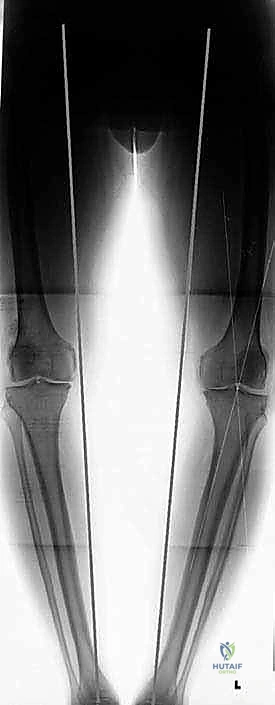

في الحالة الطبيعية الميكانيكية، يمر "محور تحمل الوزن" (Weight-bearing axis) مباشرة عبر منتصف الركبة، مما يوزع الضغط بالتساوي. ولكن، عند حدوث تقوس في الساقين (Varus Deformity)، ينزاح هذا المحور إلى الداخل، مما يضع ضغطاً هائلاً ومدمراً على الغضروف الداخلي للركبة.

هذا الضغط المستمر يؤدي إلى تآكل الغضروف بشكل أسرع من الطبيعي، مما يسبب احتكاك العظم بالعظم، وهو ما يُعرف بخشونة الركبة. هنا يأتي دور الجراحة لإعادة توجيه هذا المحور نحو الجزء الخارجي السليم من الركبة.

تُعد الأشعة السينية (X-rays) الممتدة من الحوض إلى الكاحل (Scanogram) ضرورية جداً لحساب زاوية التقوس بدقة وتحديد مقدار التعديل المطلوب جراحياً.

قبل العملية، يتم قياس زوايا الركبة بدقة متناهية. كل درجة من درجات التعديل يتم حسابها مسبقاً.

استخدام التخطيط الرقمي يضمن عدم حدوث تصحيح مفرط (Over-correction) أو تصحيح ناقص (Under-correction)، وهو ما يميز الجراح الخبير عن غيره.